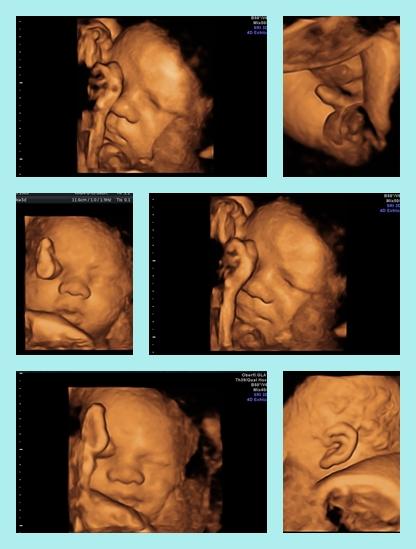

hey steffi, willkommen zurück die restlichen mankos werden sich auch schnell legen, ich drück jedenfalls die daumen!!!! und sind deine großen auch schon ganz enzückt von der kleinen mila? die sind bestimmt auch froh ihre mama wieder bei sich zu haben. hab dir noch ein bildchen drangehängt, du hast es nicht mehr gesehen weil du schon in der klinik warst :o) ganz liebe grüße

Bild zu